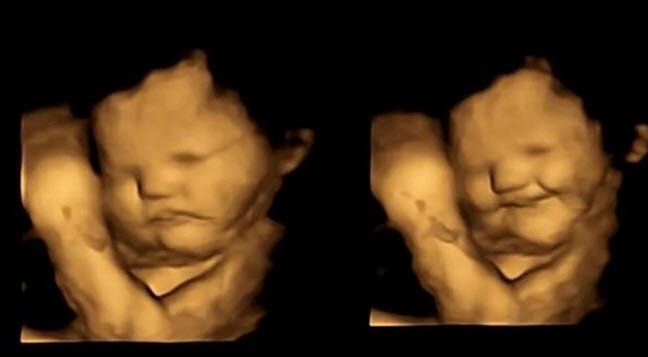

u003cbu003eANNE KARNINDAKİ BEBEKLER ANNELERİ HAVUÇ YİYİNCE GÜLÜMSÜYORu003c/bu003eYeni bir araştırma, bebeklerin daha anne karnındayken farklı tatlara tepki vermeye başladığını gösterdi. Durham Üniversitesi'nden araştırmacılar, 100 hamile kadın üzerinde yaptıkları çalışmada, dört boyutlu ultrasonla anneleri sebze yediğinde bebeklerin verdikleri tepkileri ölçtü. Sonuç dikkat çekiciydi!

Bebekler, anneleri havuç yedikten kısa süre sonra gülümserken, anneleri lahanayı tercih ettiğinde yüzlerini buruşturdu. Bulgular, hamile kadınların yediklerinin doğumdan sonra bebeklerinin tat tercihlerini etkileyebileceğini gösteriyor. Araştırmacılara göre, sonuçların sağlıklı beslenme alışkanlıkları oluşturmada etkileri olabilir.

ARAŞTIRMA EKİBİNİN BAŞINDA BİR TÜRK VARKadınlar havuç yediğinde fetüsler gülümserken, laha kapsülü fetüslerin yüzlerini buruşturmalarına yol açtı. Araştırmayı yapan ekibin başındaki isim Beyza Üstün'dü. Üstün, Henüz doğmamış bebeklerin lahana ve havuç tatlarına verdiği tepkileri görmek ve bunları ebeveynleriyle paylaşmak inanılmazdı dedi.

u003cbu003eANNE KARNINDA TAT ALABİLİYORLARu003c/bu003eDaha önceki çalışmalar, amniyotik sıvının solunması ve yutulması yoluyla bebeklerin tat aldığını ve kokladığını ortaya koymuştu. Bu çalışmalar doğum sonrası sonuçlara dayanıyordu.Yeni yapılan araştırma ise bebeklerin doğumdan önce tatlara verdikleri tepkileri değerlendirerek anne karnında tat alıp alamadıklarını test etti.Yaşları 18 ile 40 arasında değişen 100 hamile kadın, hamileliklerinin 32'nci haftası ile 36'ncı haftası arasında dört boyutlu ultrasonla takip edildi. Kadınlara her ultrason taramasından 20 dakika önce 400 mg havuç ve 400 mg lahana kapsülü verildi; bu esnada başka bir şey yiyip içmemeleri istendi. Kontrol grubundaki bazı kadınlara ise her iki kapsül de verilmedi. Sonuçlar, düşük miktarda havuç ve lahananın anne karnındaki bebeklerin tepki vermesi için yeterli olabileceğini gösterdi.